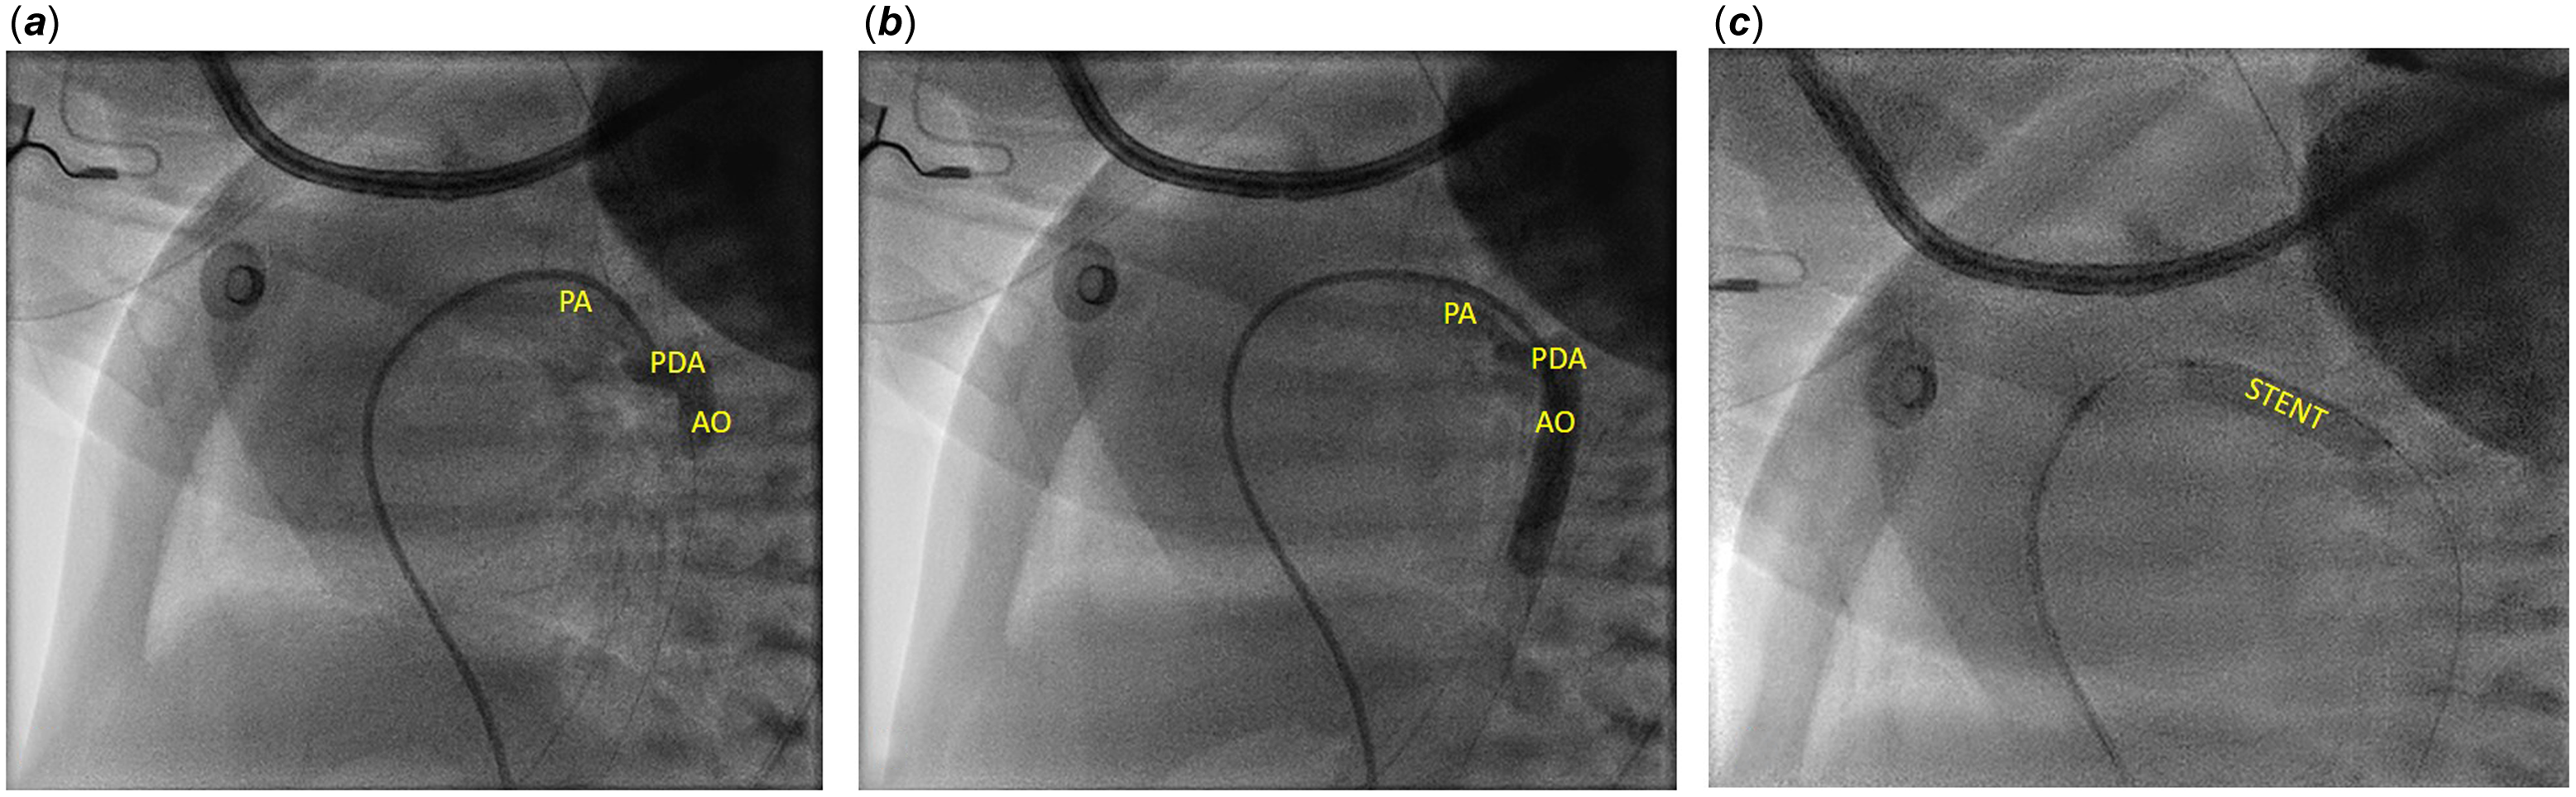

Patent arterial duct was crossed from the pulmonary side, with a 0.014” coronary guidewire. The TorqVueTM LP catheter was advanced up to the aorta, where the angiographies showed a tortuous patent arterial duct with knees, one on the proximal side and the other one on the distal side (Figure 1). The total duct length was of 18 mm. A 4x20 mm bare coronary stent (RebelTM Boston Scientific, Marlborough, MA, USA) was advanced directly inside the TorqVueTM LP catheter and successfully deployed. Post-implant angiography showed a good stent placement, as did the echocardiography, and a mild protrusion, not haemodynamically significant, in left pulmonary artery. A 5mg/kg aspirin therapy was started.

Figure 1. A. and B. Angiography performed with 4 Fr TorqVueTM LP catheter. C. Coronary Rebel stent implanted using 4 Fr TorqVueTM LP catheter. AO = aorta; PDA = patent ductus arteriosus; PA = pulmonary artery; STENT = stent.